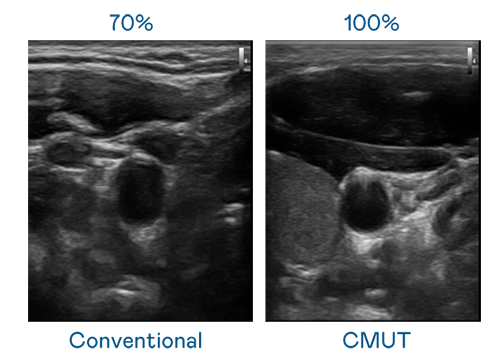

CMUT 技术是一种用电容式微机电元件来产生超音波讯号的技术。与传统 PZT 压电式技术相比,CMUT 频宽增加 30%,更宽频的超音波讯号让影像解析度大幅提升,是实现高影像品质医疗超音波扫描、促进精准医疗发展的关键技术。

超音波影像的解析度高低,首先取决于探头能发出的讯号频宽。z6mg人生就是博 CMUT 可提供高清晰的超音波讯号,提供高频宽、高灵敏度、影像纹理细节更高的超音波影像,协助医护人员缩短影像判读时间及利用精准的医疗影像进行诊断。